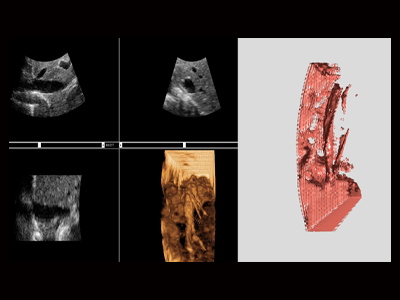

智能AI引导下的3D/4D高级应用

基于GPU平台的超声实时3D/4D成像

可以快速的进行三维数据重建,并实时绘制三维数据,形成预期结果

针对成像的结果

以人为选定修改成像区域,去除皮肤、肌肉等对成像结果 造成干扰的组织结构

通过GPU和CPU的配合

保持计算精度的同时显著提升了三维图形渲染的速度,给用户带来流畅的操作体验。